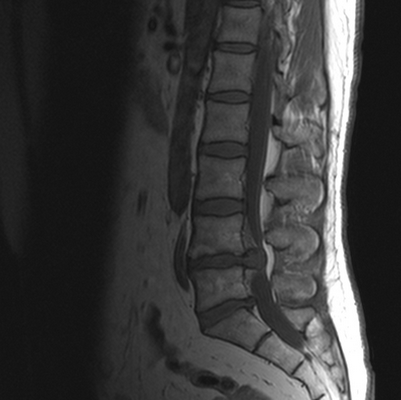

Грыжа диска между телами 4 и 5 поясничных позвонков на МРТ

МР-сканирование основано на воздействии магнитного поля. Последнее изменяет поведение атомов водорода в структуре молекул воды, которая в том или ином количестве присутствует во всех тканях. Аппарат улавливает импульсы и на основании силы последних выстраивает картинку (называемую снимком или срезом).

Основной областью применения рентгенографии является диагностика патологий позвонков. Рентген чаще используют как экспресс-метод для выявления травм и связанных с ними патологических изменений при недоступности других методов. МРТ хорошо отражает состояние мягких тканей (межпозвонковых дисков, спинного мозга, сосудов, мышц, нервов, связок).

Гигантская грыжа поясничного отдела позвоночника на МРТ

МРТ активно используют для уточнения природы заболевания, обнаружения изменений в позвоночном канале. Метод позволяет выявить опухоли, грыжи дисков, образование секвестров, компрессию спинного мозга или нервных корешков. Показаниями для проведения МР-сканирования являются: